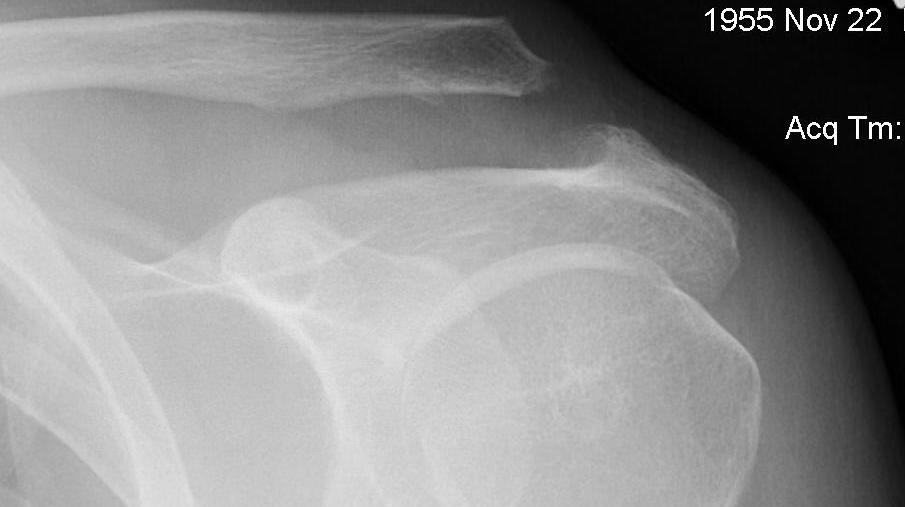

IV AC and CC ligaments disrupted and clavicle displaced posteriorly into trapezius

- can be easily missed

- need axillary lateral

Type VI / Subcoracoid dislocation

Rare / can be missed

Risk of neurovascular injury / high velocity injury / associated with multi-traumas

Requires open reduction and fixation

Subcoracoid dislocation case report